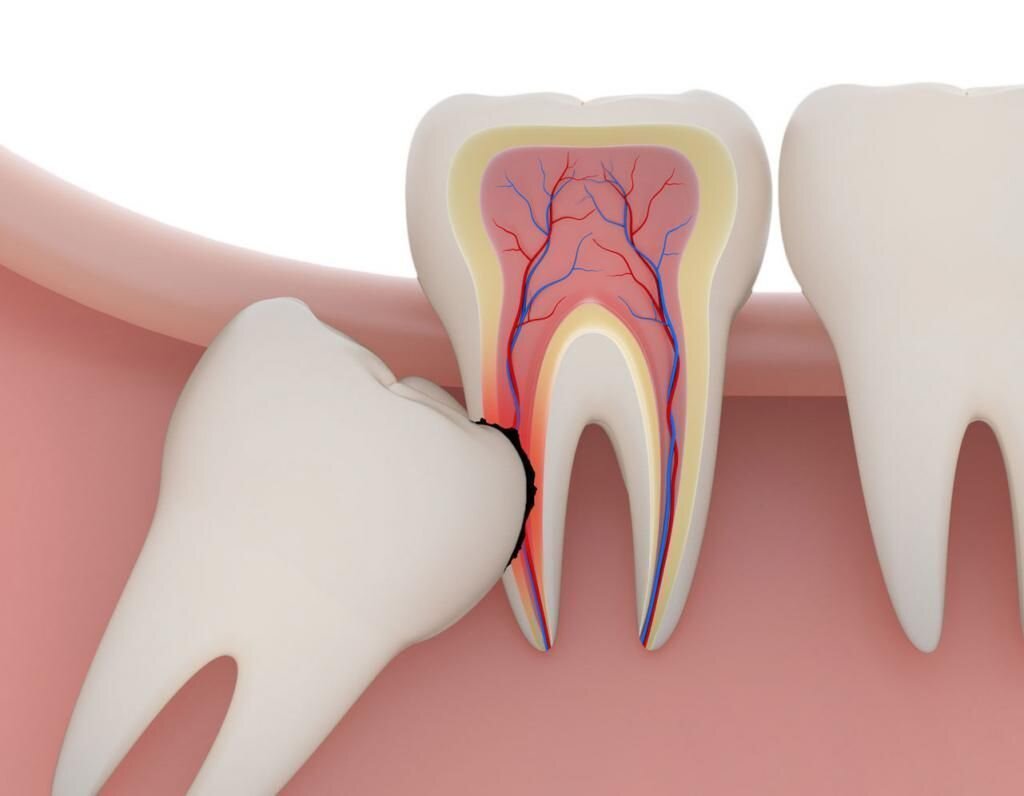

· маляр растет под углом, мешает другим зубам и доставляет дискомфорт, возрастающий во время еды;

· Кариес. Развивается быстро из-за сложностей чистки дальних зубов.